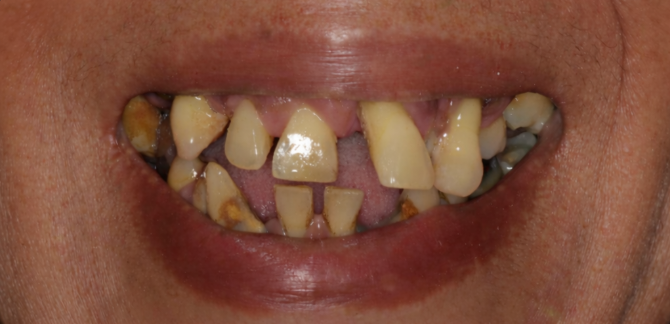

- ✔️ Cosmetic Dental Treatments